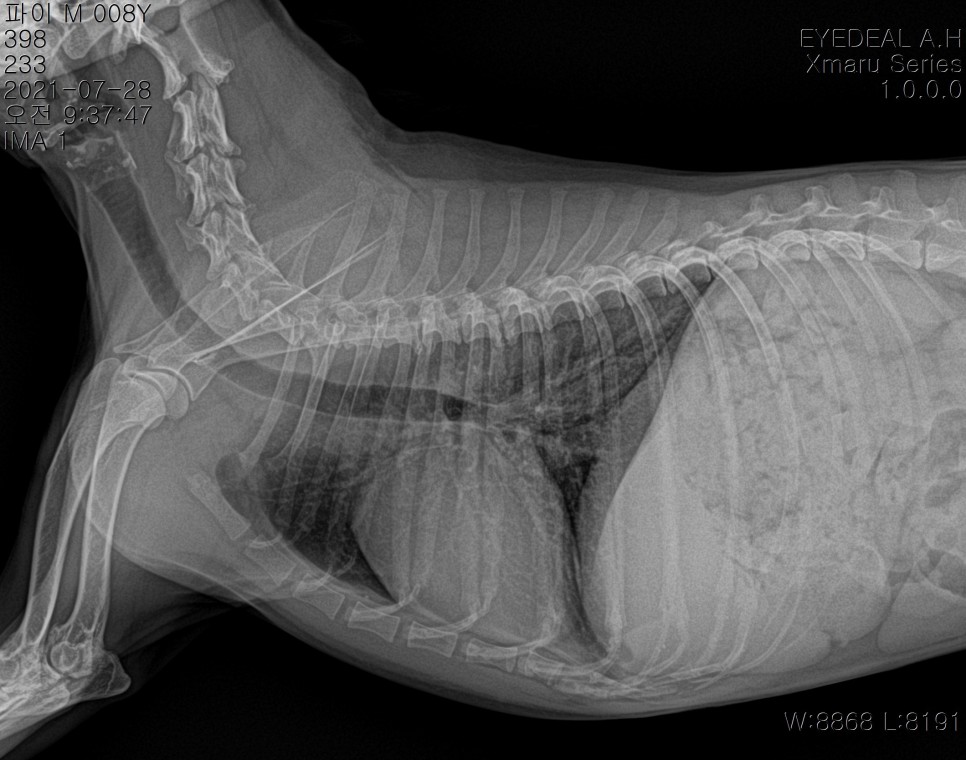

수술전검사(기본신체검사,흉복부xray,혈액검사)*흉복부x선검사

- 혈액검사(혈구검사, 혈청 화학검사) 혈당관리도 잘 되어 있는 상태이며 별다른 이상이 없으므로 충분한 수액처치 후 수술을 시행하였습니다.

당뇨병인데 수술이 가능합니까?네, 당연히 가능하죠혈당 관리가 잘 되고, 눈에 다른 문제가 없는 경우에는 다른 자녀와 마찬가지로 마취 전 검사를 실시하고 수술을 실시합니다.